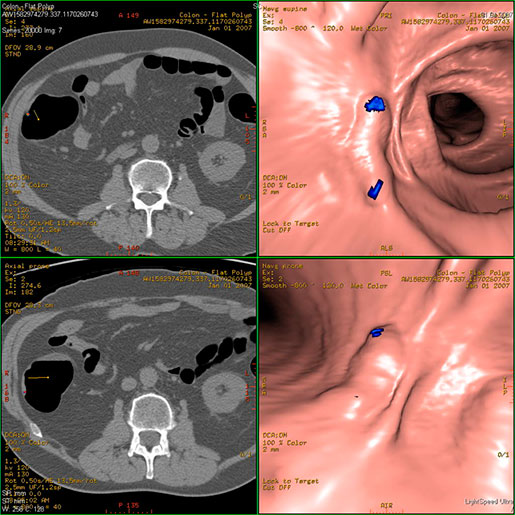

МСКТ виртуальная колонография- перспективный метод скрининга выявления колоректального рака и полипов.

Показания:

- выявление полипов и опухолей

- в качестве скрининга для практически здоровых людей

- при выраженном спаечном процессе